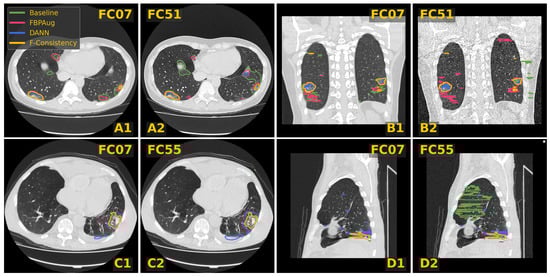

In Figure 3, we visualize predictions of the same four methods on the paired images from the Paired-private dataset. For the Baseline, we observe an extreme inconsistency (Figure 3A) and massive false positive predictions in healthy lung tissues (Figure 3D) and even outside lungs (Figure 3B). For the adaptation methods, their predictions are visually more consistent inside every pair, which aligns with the consistency scores in Table 3. Despite the high consistency scores, FBPAug and DANN output more aggressive predictions. FBPAug predicts motion artifacts near the body regions (Figure 3A) and triggers similarly to the baseline on, most likely, healthy lung tissues (Figure 3B). DANN is more conservative but triggers on the consolidation-like tissues (Figure 3C,D). However, without the ground truth annotations on the paired data, we refer to this analysis as a discussion.

Figure 3. Examples of CT slices from the Private-paired dataset with the corresponding predictions on the paired images. Four doublets, denoted (AD), contain corresponding slices from the smooth and sharp images. The doublets B and D are coronal and sagittal slices, respectively. Every slice contains predictions of four methods named in the legend.